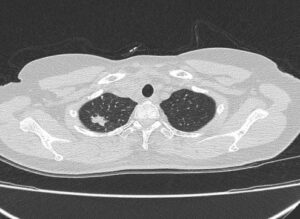

Case lâm sàng: Ứng dụng trí tuệ nhân tạo (Artificial intelligence – AI) trong chẩn đoán và điều trị sớm Ung thư phổi tại Trung tâm Y học hạt nhân và Ung bướu, Bệnh viện Bạch Mai

Case lâm sàng: Ứng dụng trí tuệ nhân tạo (Artificial intelligence – AI) trong chẩn đoán và điều trị sớm Ung thư phổi tại Trung tâm Y học hạt nhân và Ung bướu, Bệnh viện Bạch Mai GS.TS. Mai Trọng Khoa, PGS.TS. Phạm Cẩm Phương, BSNT Nguyễn Ngọc Ánh...